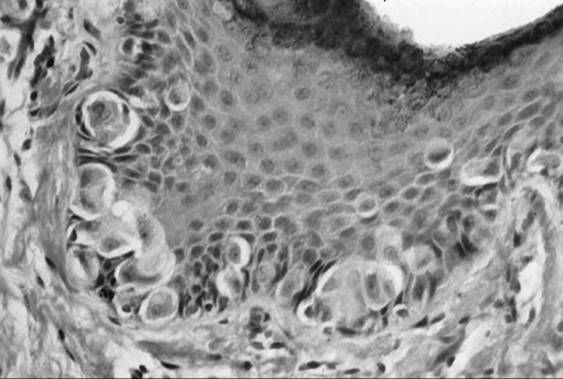

Paget Disease

Paget disease accounts for 1% to 2% of vulvar malignancies. It occurs most frequently in postmenopausal white women and is characterized by red eczematous lesions with a superficial white coating and intense pruritis. As with other vulvar malignancies, there may be a long delay between initial symptoms and diagnosis. Histologic disease may spread well beyond the visible lesion. Biopsy reveals characteristic large eosinophilic cells in the basal layer of the epithelium (Fig. 51.12). Paget disease of the vulva may exist as four clinical entities, the first of which is noninvasive or intraepithelial Paget disease. This represents 60% of cases and is cured with local excision. In invasive Paget disease, the Paget cells penetrate the basement membrane and invade the dermis. Intraepithelial Paget disease may also be associated with an underlying adenocarcinoma of sweat gland origin or a coexistent cancer. Underlying malignancy is seen in approximately 20% to 30% of patients, a rate lower than that seen with mammary Paget disease. Parker and co-workers reported poor survival in patients with invasive Paget disease and in patients with underlying malignancy. Patients with clitoral disease also had a poorer prognosis. Therapy for Paget disease involves wide excision. A skinning vulvectomy with split thickness skin graft is often needed to remove large areas of involved skin. Recurrences tend to be local and range from 7% to 58% with an average of about 30%. Some authors recommend sending margins for frozen section to ensure complete resection while others have not demonstrated a benefit to this approach with respect to recurrence. Radical surgery is reserved for patients with underlying malignancy.

FIG. 51.12. Paget disease of the vulva. Large eosinophilic cells with large nuclei and prominent cytoplasm in basal cells represent Paget cells.